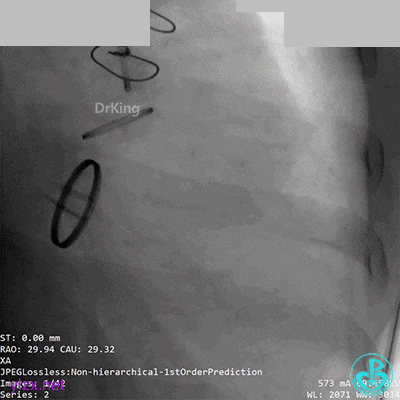

05 急诊冠脉造影

前降支血流3级,前降支近段、对角支开口大量血栓,回旋支开口闭塞。